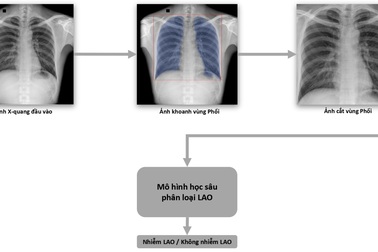

VinBrain và FIT phát hành sách trắng ứng dụng AI cho chuẩn đoán và tầm soát bệnh laoNgày 4/6 vừa qua, Công ty VinBrain (Tập đoàn Vingroup) và FIT (Tổ chức phi chính phủ trong lĩnh vực phòng và chống Lao) công bố sách trắng về ứng dụng trí tuệ nhân tạo (AI) cho chẩn đoán và tầm soát bệnh lao tại Việt Nam.

DrAid™ - "trợ lý AI" đầu tiên tại Đông Nam Á đạt chuẩn FDA Hoa KỳSản phẩm DrAid™ của VinBrain vừa chính thức được FDA Hoa Kỳ ra công văn chấp thuận. Đây cũng là sản phẩm AI cho chẩn đoán X-quang đầu tiên và duy nhất tại Đông Nam Á sở hữu chứng nhận quan trọng này.